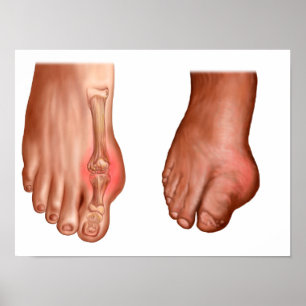

Poster Anatomie D'Un Pied Gonflé

Prix25.40 CHF